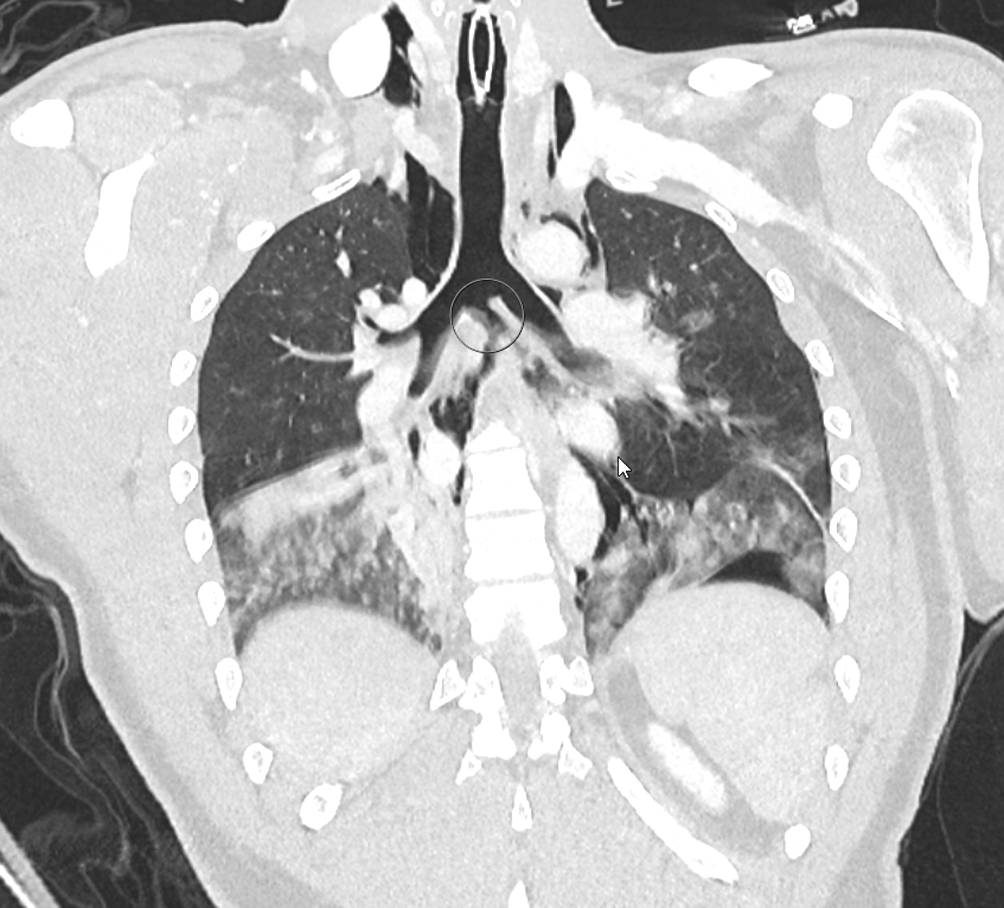

Abb. 1

Computertomographische 3‑D-Rekonstruktion des Schädels mit komplexen Mittelgesichtsfrakturen (LeFort-I-Fraktur rechts komplett, links inkomplett, LeFort-II-Fraktur rechts und LeFort-III-Fraktur beidseits)

Bei nun stabiler Kreislaufsituation (ohne Volumen- oder Noradrenalingabe) und gemäß aBGA ausreichender Oxygenierung und Ventilation entschieden wir uns, zunächst einmal auf die Anlage von Thoraxdrainagen zu verzichten und die bildgebende Diagnostik durch eine Computertomographie (CT) zu vervollständigen. Diese zeigte im Wesentlichen komplexe Mittelgesichtsfrakturen (LeFort-I-Fraktur rechts komplett, links inkomplett, LeFort-II-Fraktur rechts und LeFort-III-Fraktur beidseits, Abb. 1), nichtdislozierte Frakturen der Processi transversi des Halswirbelkörpers (HWK) 7 und der Processi transversi der Brustwirbelkörper (BWK) 1 und 2 rechts, einen schmalen beidseitigen Hämatopneumothorax mit maximaler Saumbreite von 2,5 cm, Rippenserienfrakturen beidseits (Costae I–VII rechts, Costae I–IX links) mit Flail-Segment rechts (Costae I–VII jeweils mehrfach zwei- oder dreifach frakturiert), eine Lungenkontusion und -lazeration beidseits sowie ein Pneumomediastinum (Abb. 2). Bis auf die genannten Querfortsatzfrakturen fand sich keine weitere Wirbelsäulenverletzung, das Alignment war über die komplette Wirbelsäule intakt.